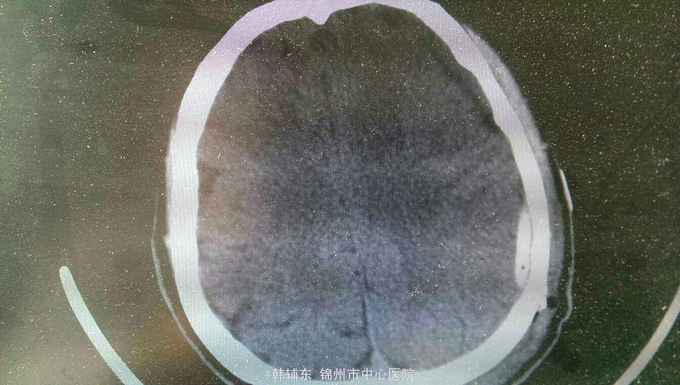

神志清楚,语言流利。神经系统无阳性体征,双侧瞳孔等大正圆直径3.0毫米,光反射灵敏。四肢肌力正常,生理反射存在,病理反射未引出。头部核磁共振显示如下。

诊断:亚急性硬膜下血肿。行血肿钻孔引流术。术后引出陈旧血,患者头痛缓解。

亚急性性硬膜下血肿绝大多数有轻微头外伤史,尤以老年人额前或枕部着力。亚急性颅内压增高症状常于伤后1~3个月后出现如头痛、视物模糊、一侧肢体无力等。精神智力症状表现为记忆力减退、智力迟钝、精神失常等。局灶性症状表现为轻偏瘫、失语等。亚急性或慢性硬膜下血肿MRI的T1和T2均表现为高信号。首选颅骨钻孔冲洗闭式引流术。对于血肿囊壁肥厚伴钙化须行骨瓣开颅清除血肿术。